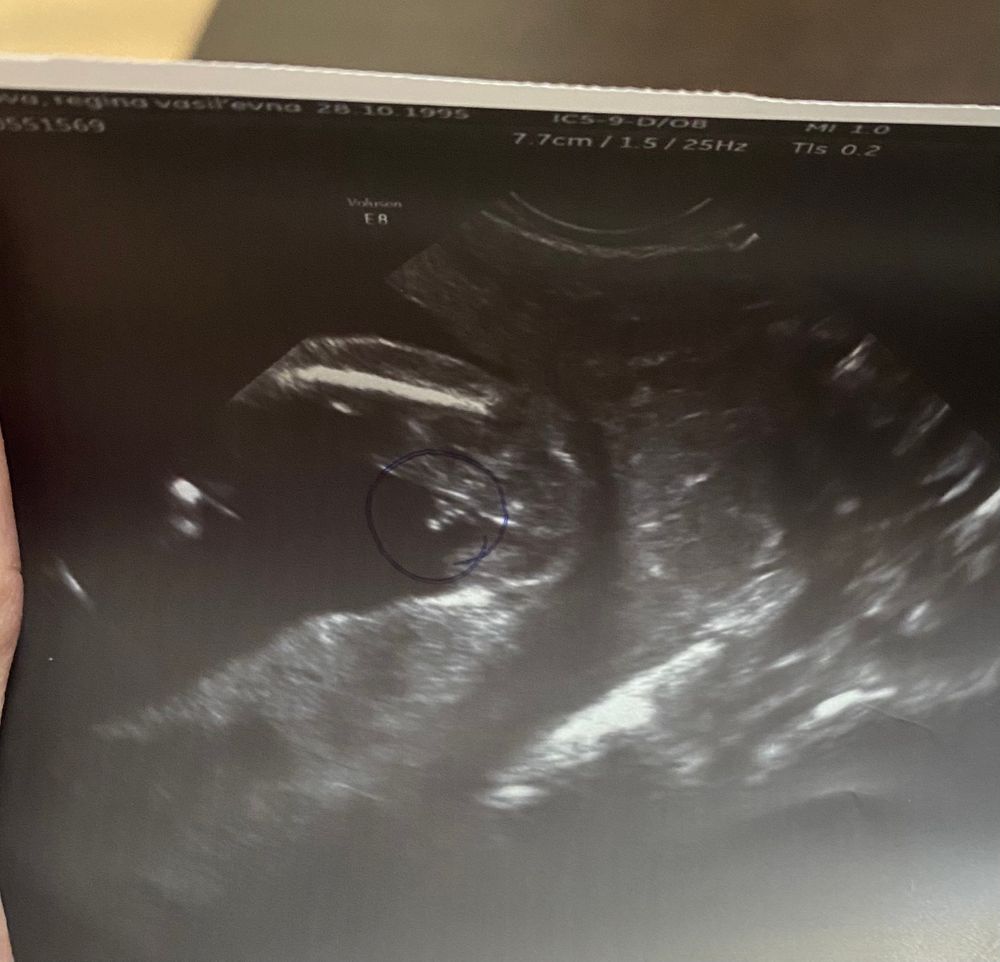

На память. Второй скрининг. Пол 🙈

Пошла наша 21 неделя, сегодня была на скрининге. В итоге у нас не мальчик, а девочка. Такие дела 😃💓

Развивается согласно сроку, все хорошо, слава Богу. Весим мы почти 400 грамм. Шейка 35 мм.

Valentina , вот 😀

Врачи уже после этого узи говорили, что скорее всего это был клитор😅